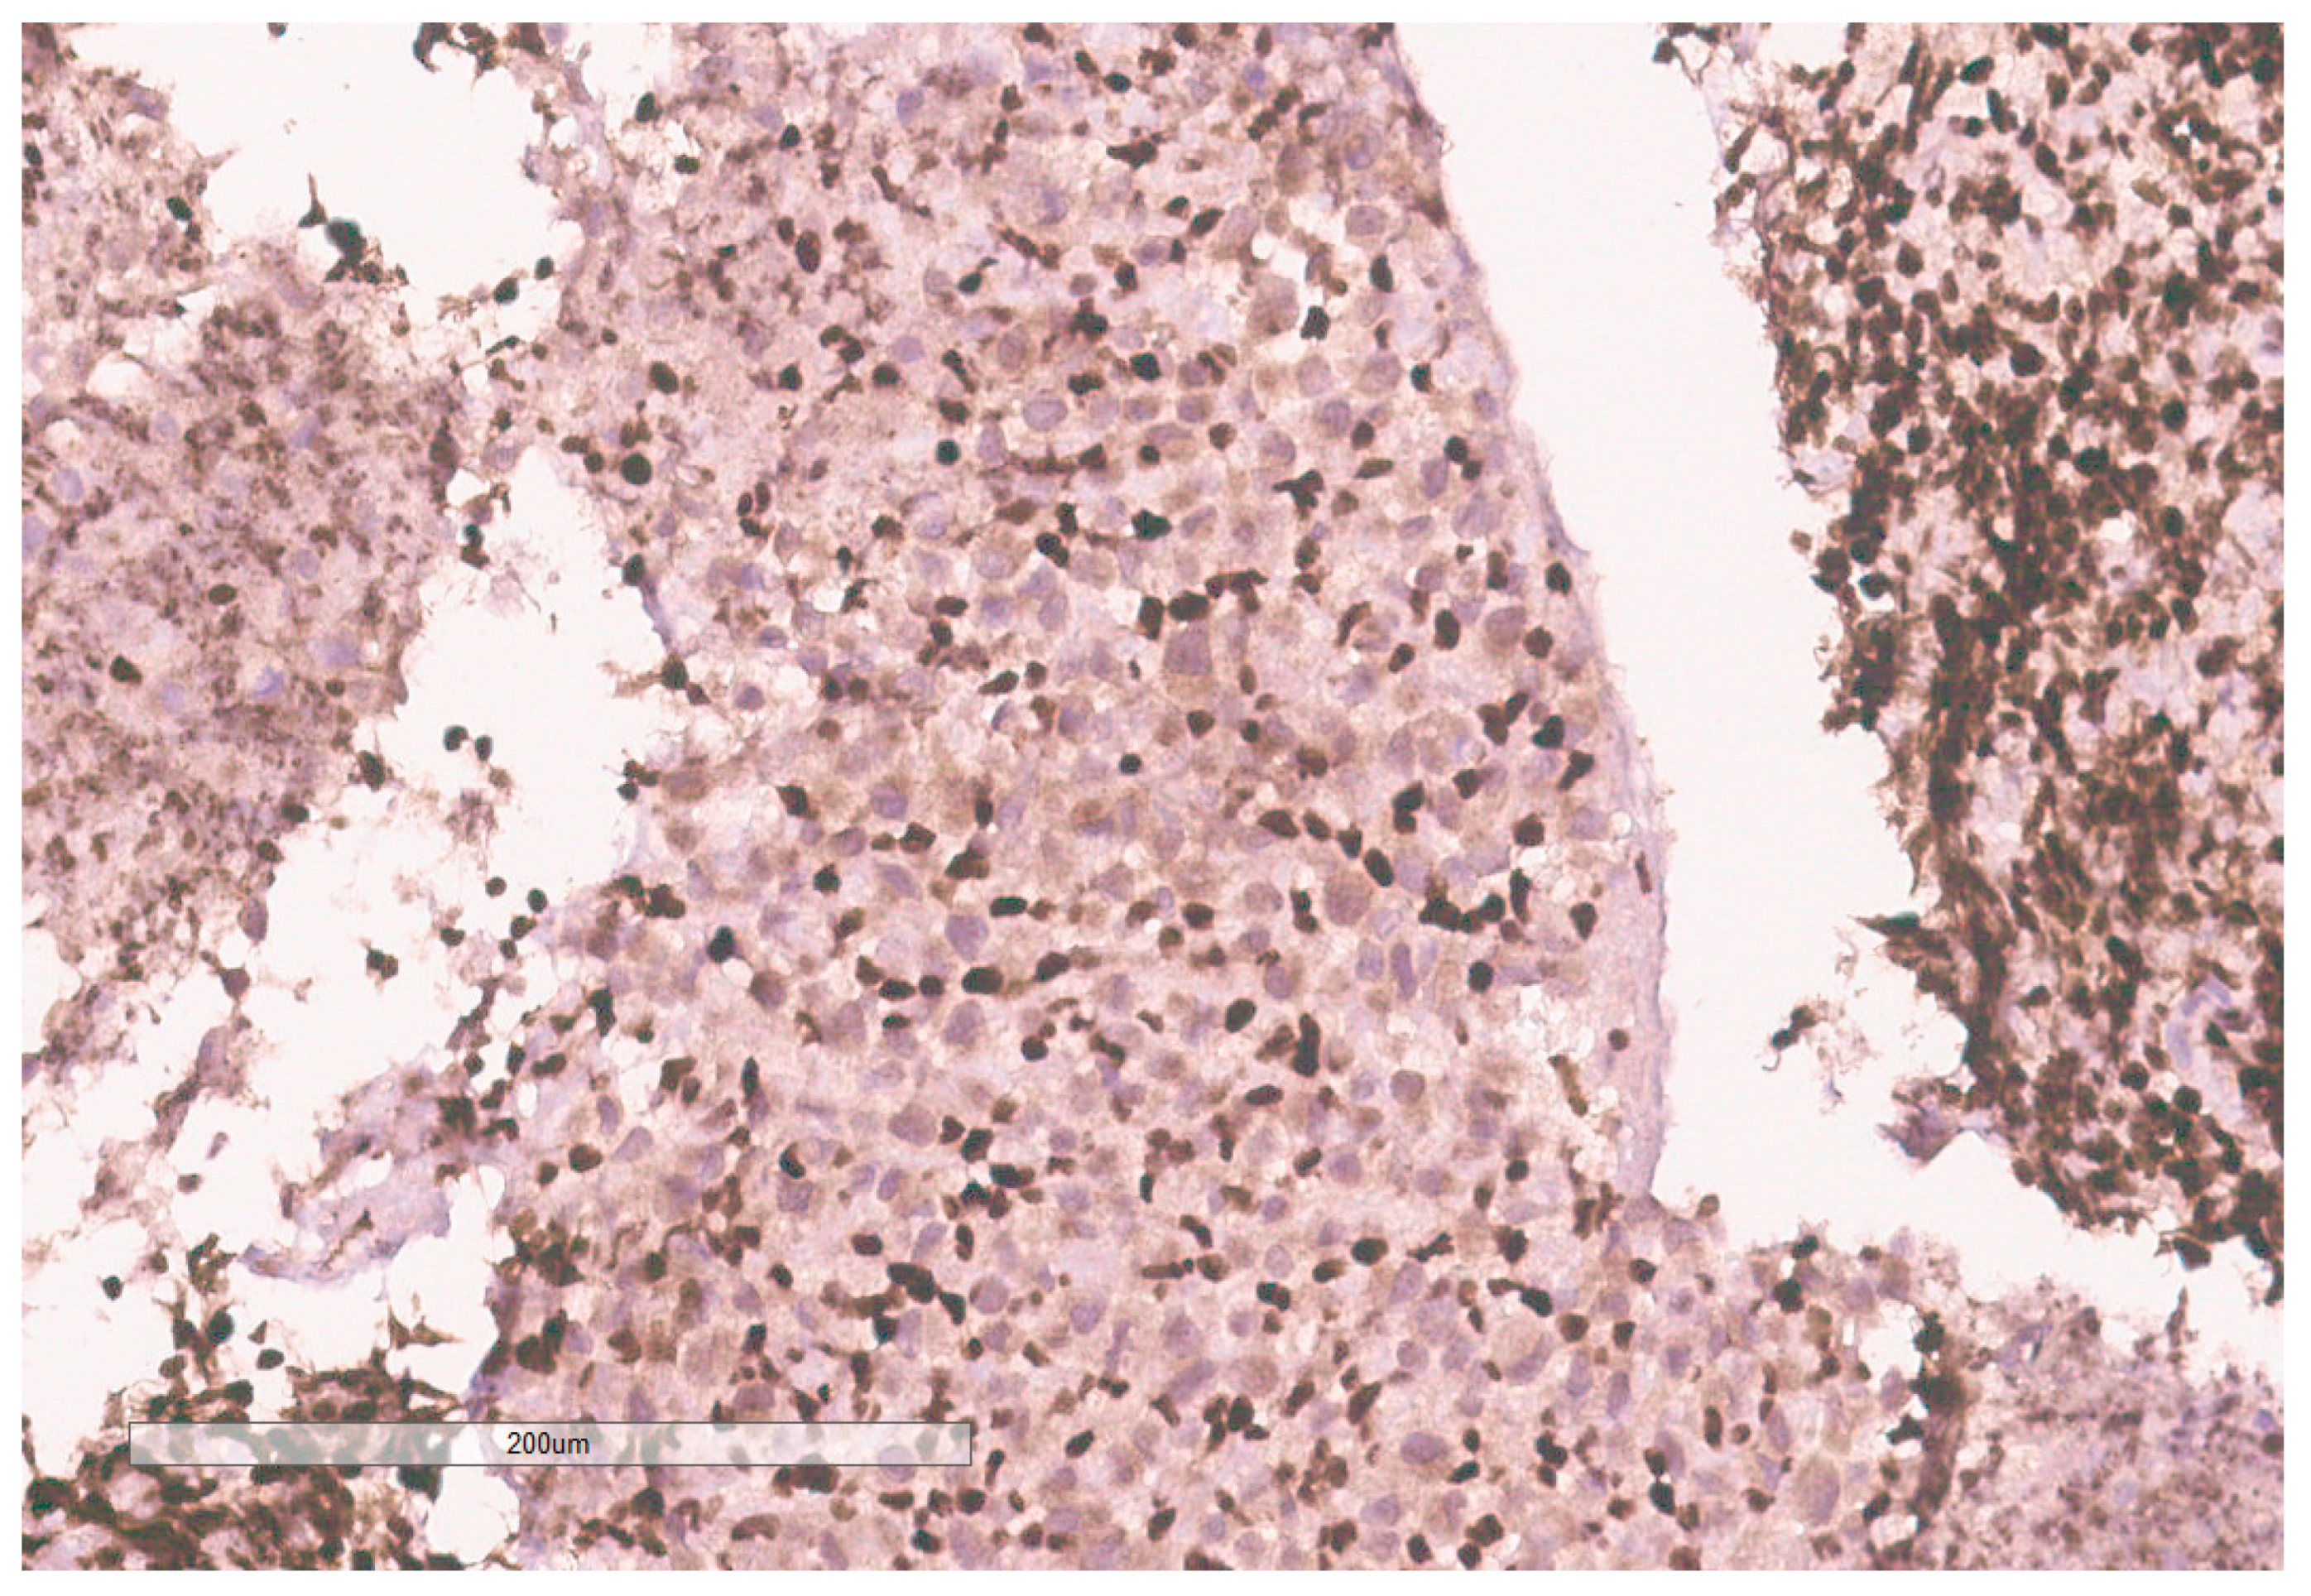

The biopsy of right kidney demonstrated mostly fibrinous material with small fragments of renal parenchyma with interstitial chronic inflammation and no definite tumor. The biopsy of a retroperitoneal lymph node showed high grade tumor composed of discohesive rhabdoid cells with highly atypical nuclei and eosinophilic cytoplasm involving lymphoid tissue with areas of necrosis and neutrophilic inflammation with necrosis and limited viable tumor cells (Figure 7). By immunohistochemistry, the cells were positive for pankeratin (Figure 8) and PAX8 (Figure 9) and negative for CK7, CK20, GATA3, CDX2, TTF1, CAIX, ERG, S100, CD34, CD30, SMA, desmin, OCT3/4 and CD163. The tumor cells showed diffuse loss of SMARCB1/INI-1 (Figure 10). The INI-1 was reviewed by several experienced pathologists that interpreted the stain as negative. While there is some background cytoplasmic and nuclear staining in the entire specimen, the norm is to compare staining with the adjacent internal positive control. Given that, in this case, the lymphocytes stained strongly positive for INI-1, it was appropriate to interpret this is as a negative stain in this context. As evidenced by the high-power image, the staining appears to be of a background variety and limited to the cytoplasm, in which the nuclei remain negative. Hence, this is interpreted as a negative stain.

Figure 10. INI-1 (BAF47) is negative in the tumor. Lymphocytes serve as an internal positive control.